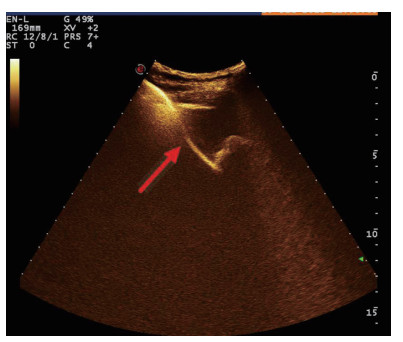

均采用塞丁格(Seldinger)技术置入引流管(图 4):穿刺穿刺点的选择①左侧卧位,超声确定胆囊床方位,取腋前线肋间或肋缘下进针; ②经肝的路径长度应大于2.0 cm胆囊穿刺点为中上部距离胆囊颈约1 /3的位置; ③穿刺路径上尽量避开大血管及大胆管结构; ④结合术前经肘静脉超声造影情况,避开胆囊穿孔部位及周边黏连组织。操作过程:由超声介入治疗组专业医师单人操作,为获得更自由的穿刺角度以及在穿刺过程中根据患者呼吸活动随时对进针角度进行调整,本组操作均未使用超声探头引导架。操作步骤①常规碘伏皮肤消毒,2%利多卡因局部麻醉至肝脏被膜。操作医师一手持超声探头,清晰显示进针入路,一手持18 G PTC穿刺针经皮经肝由胆囊床穿刺进入胆囊,拔出针芯,可见胆汁自行流出或用20 mL注射器回抽见胆汁。②沿针鞘置入导丝,超声探查见导丝进入胆囊,拔出针鞘。③扩张器扩张针道。④根据抽出胆汁的混浊程度,沿导丝置入合适型号的引流管,确定引流管通畅后拔出导丝,拉紧猪尾导管的外置固定线,使导管弯曲头牢固卷曲,形成内固定,皮肤缝线外固定引流管,双重固定更加有利于引流管留置于可靠位置,有效避免脱管。术后再次皮肤消毒,覆盖无菌贴膜。接引流袋。⑤术中及术后半h均予心电监测,术后常规送胆汁细菌培养,密切观察患者症状体征改善情况。

| 图 4 胆囊置管过程,导丝进入胆囊腔内(箭头处) |